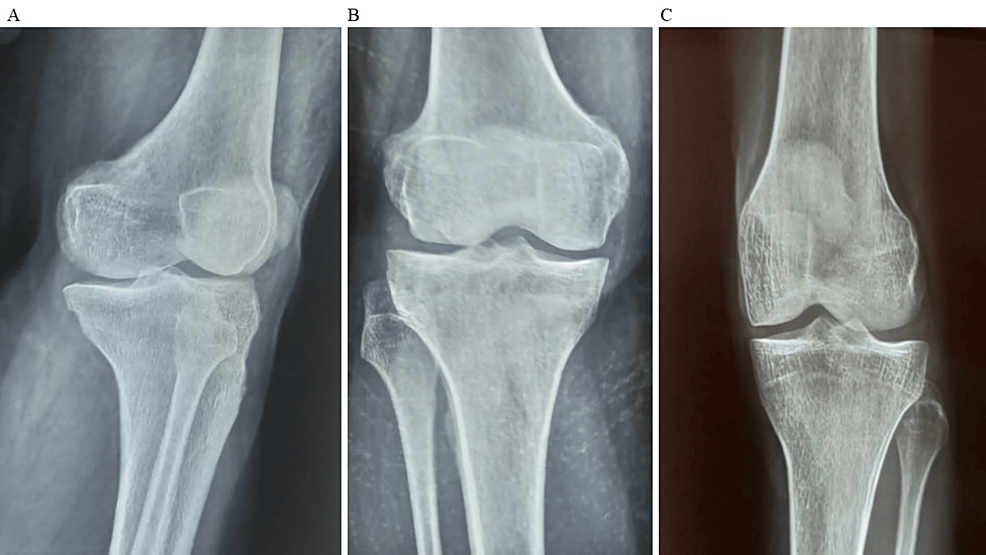

平均WOMAC評(píng)分從基線時(shí)的56.8±11.5下降到六個(gè)月時(shí)的41.2±10.6。此外,還監(jiān)測了不良事件的發(fā)生情況,報(bào)告了七起不良事件,占參與者的28.0%。這些發(fā)現(xiàn)強(qiáng)調(diào)了該治療在六個(gè)月內(nèi)減輕疼痛和改善功能結(jié)果方面的有效性。下圖2顯示了開始干細(xì)胞治療后骨骼的側(cè)視圖和前后視圖。?